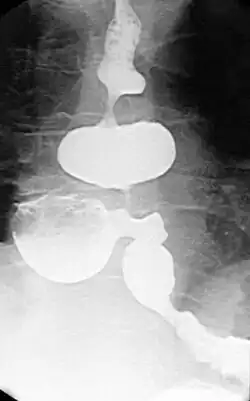

Barsony-Pseudodivertikel

Als Barsony-Pseudodivertikel werden die veränderlichen Ausbuchtungen der Speiseröhre zwischen zwei spastischen Kontraktionen bezeichnet, die beim diffusen Ösophagusspasmus auftreten. Sie können von echten epiphrenischen Divertikeln begleitet werden, die auch bestehen bleiben, wenn gerade keine Kontraktionen ablaufen.